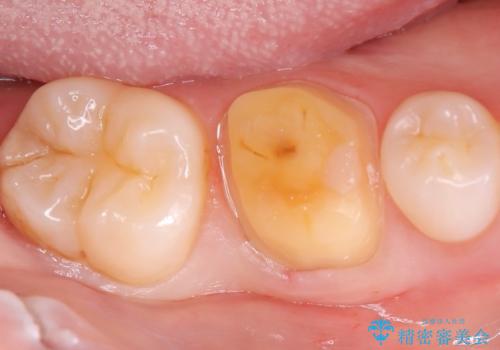

歯が欠けた <セラミッククラウン>

- 主訴は、歯が欠けてしみるとのことでした。欠けた部分が大きいことから、被せものでの治療をおすすめしました。

審美性の良いオールセラミッククラウンを選択されました。